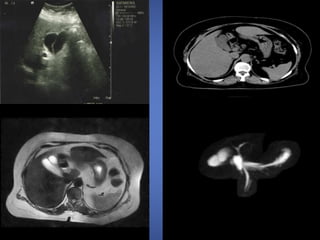

Newborns and infantspresent with obstructive jaundice. Older children and adults may have the classic triad of right upper quadrant pain, intermittent jaundice, and a palpable right upper quadrant mass. In adult patients, a choledochal cyst is often first diagnosed on cross- sectional imaging. CT and ultrasound demonstrate a fluid-filled structure beneath the porta hepatis separate from the gallbladder that communicates with the hepatic ducts. An abrupt change in the caliber of the ducts occurs at the site of the cysts. Intrahepatic ductal dilatation may be present as well.

• 56.

Ultrasound May show dilatedintrahepatic bile ducts (IHBD). intraductal bridging: echogenic septa traversing the dilatedbile duct lumen. smallportal venous branches partially/completely surroundedbydilatedbile ducts. intraductal calculi. CT multiple hypodense rounded areas which are inseperable from the dilated intrahepatic bile ducts “centraldot” sign: enhancing dots within the dilated intrahepatic bile duct s, these intraluminal dots correspond to intraluminal portal veins

• 57.

MRCP with three-dimensionaldisplay is an accurate method for demonstrating Caroli’s disease because the luminal contents of the bile ducts appear hyperintense in contrast to the portal vein, which usually appears as signal void. Cystic expansions of the intrahepatic biliary tract are depicted as oval- shaped structures in continuity with the biliary tract.